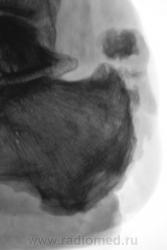

остиомиелита не видно а вот шпора знатная..

остеомиелит пяточной кости.

Валентин Львович, так всё-таки расценили как остеомиелит?.. Не увидел периостальной реакции, смазанности/лизиса (участков) кости, а вижу уплотнение мягких тканей (качество снимка, не отёк)...

Остеомиелит. Есть краевая деструкция бугра, чередование пороза/склероза.

Лечат от остеомиелита, но безуспешно. По всей видимости, пациент поедет в областную.

Валентин Львович, будьте любезны, опишите местный статус, насколько давно возникла клиническая картина. По снимкам - согласна с Сан Санычем: скорее - ткань, чем +ткань, т.е. есть ли изъязвления, открытая раневая поверхность. Поясняю6 такая картина м.б. не только при гнойно-воспалительных процессах, но и при опухолях кожи (например - плоскоклеточный рак, меланома). Длительно существующие воспалительные процессы нередко сочетаются (или осложняются) с опухолью, по-видимому происходит постепенная метаплазия.

Да, имеется изъязвленная поверхность, из которой выделяется не приглядного вида содержимое, весьма дурно пахнущее, процесс существует около 1,5 лет. Наши хирурги лечат или не лечат - не знаю, сейчас, данный пациент лечится амбулаторно, ранее, около месяца находился в хирургическом отделении.